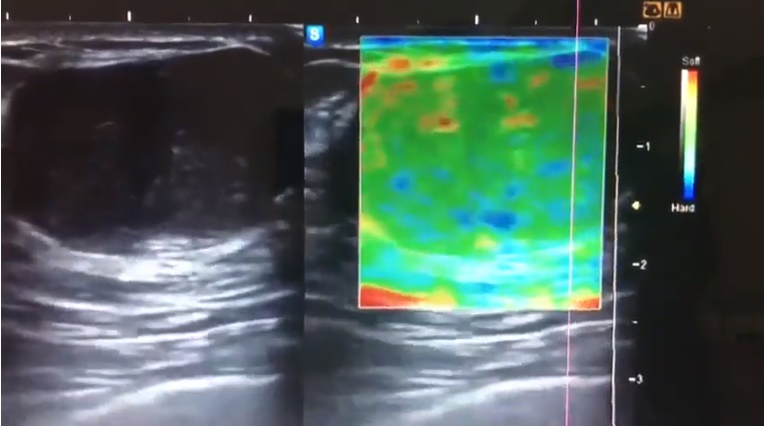

Valores normales de elastografía método ARFI en pacientes sin antecedentes patológicos:

Valores normales de elastografía método ARFI en pacientes sin antecedentes patológicos: cabeza y cuello (glándulas parótidas, glándulas submandibulares y tiroides). En conjunción con la imagen ecográfica, aparece una nueva técnica de imagen con nuevas...